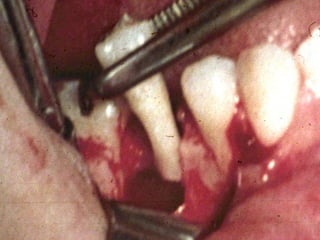

Plastia de maxilares para implantes dentales.

La conformación quirúrgica de un contorno alveolar adecuado es

determinante para la correcta aplicación y aceptación de los implantes

de titanio, aquí proponemos una técinica para lograr el espesor óseo

suficiente y la corrección estética del proceso, ya que antiguamente al

extraer un diente se acostumbraba presionar las tablas alveolares

“para cohibir la hemorragia”, con el colapso subsiguiente de la región.

Plastia de maxilarespara implantes dentales.

La conformación quirúrgicade un contorno alveolar adecuado es determinante para la correcta aplicación y aceptación de los implantes de titanio, aquí proponemos una técinica para lograr el espesor óseo suficiente y la corrección estética del proceso, ya que antiguamente al extraer un diente se acostumbraba presionar las tablas alveolares “para cohibir la hemorragia”, con el colapso subsiguiente de la región.